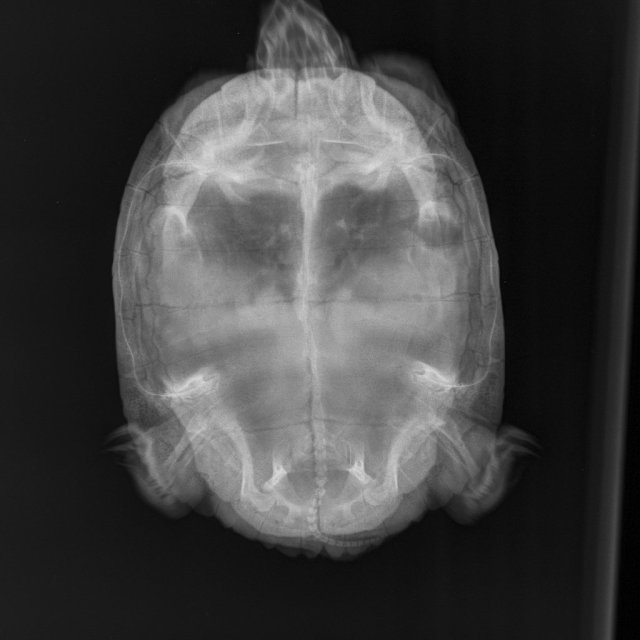

Я из Москвы, мне 49 лет. Черепаха красноухая, 10 лет, вес 1 кг 700 гр. живёт в аквариуме большом, есть лампа УФ и накаливания (включены целый день, меняем раз в полгода), есть фильтр внешний, нагреватель, мостик, грунта нет. Очень вялая - целый день отдыхает или спит, есть особо не хочет - рептомин не ест, грудку или печень раз в 5 дней после уговоров может съесть порцию небольшую, меньше чем её голова. Заметили болезнь уже недели три назад, две недели делали уколы. Последний укол 16 апреля. Прокололи курс лекарств по совету герпетолога - Кальций борглюконат через день,  Витам (1 раз в 3 суток), дексаметазон, фуросемид. По старому рентгену герпетолог сказал, что возможно яйца жировые, по свежему рентгену он никаких яиц не видит. Сейчас ничего больше не назначили нам. Я очень за черепаху волнуюсь

Мягкие ткани Мелкий _ 10 kg-Брюшная полость VD-19.04.2025-19_58_38-378.JPEG

Мелкие животные_Рептилии-Брюшная полость VD-19.04.2025-19_58_41-685.JPEG

Рентген 2 нед назад (2).JPEG

Рентген 2 нед назад.JPEG

Рентген 2 недели назад.JPEG

по симптомам нужно исключать/подтверждать анемию и проблемы с печенью. К сожалению дистанционно тут ничем не помочь. Вы сделали ей курс уколов кальция - если бы там была рядовая проблема авитаминоза/формирования яиц, то это бы помогло.